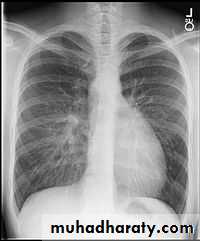

Normal chest XR PA & lateral view

1,2,3 .presentation4.normal chest film ( PA ) view

8.normal chest XR PA & lat. view

9.normal radiologic anatomy of the chest

10.normal chest anatomy